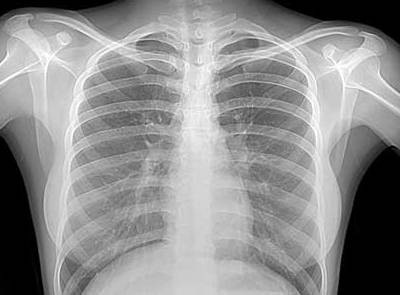

- Рентген грудной клетки.

Рентген